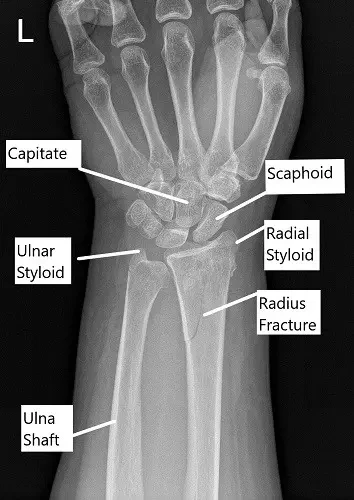

X-ray showing distal radius fracture in AP view.

The x-ray of the left wrist revealed an oblique fracture of the distal left radius which communicates with the articular surface. There is a nondisplaced fracture of the distal left ulna. Further radiological studies in the form of CT scan revealed rotation of the distal fragment, with approximately 24 degrees of resulting apex-volar angulation.